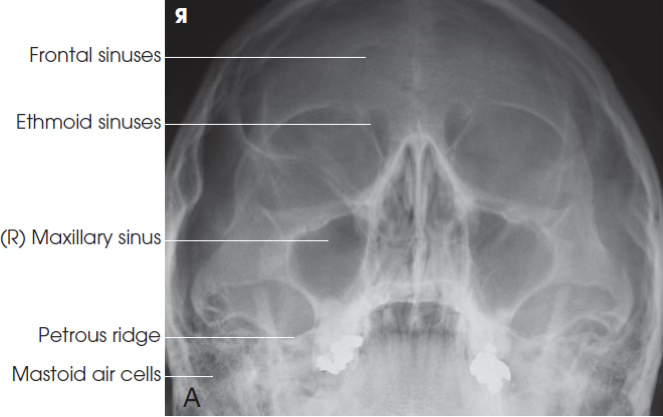

PA Axial Caldwell sinus

PA Axial Sinus (Caldwell) part position

OML perpendicular to IR

PA Axial Caldwell Sinus central ray

15 degrees caudal exiting nasion

PA Axial Sinus collimation

6x6

PA Axial Sinus evaluation

Petrous ridges in lower third of orbits

PA Axial Sinus sinus demonstrates…

Frontal sinuses